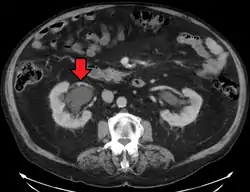

CT scan of bilateral hydronephrosis due to a bladder cancer